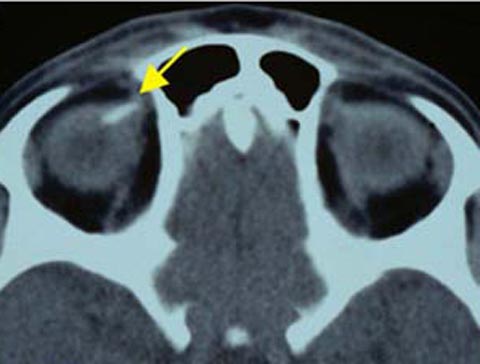

44 year old man with 2 months of painless progressive visual loss OD

36 year old man with redness, discharge and blurred vision in the left eye

57 year old woman who complains "The lids are somewhat down"

7 year old girl with a left face turn and binocular diplopia

29 year old man with visual symptoms and headaches

19 year old man with a "corneal abrasion"